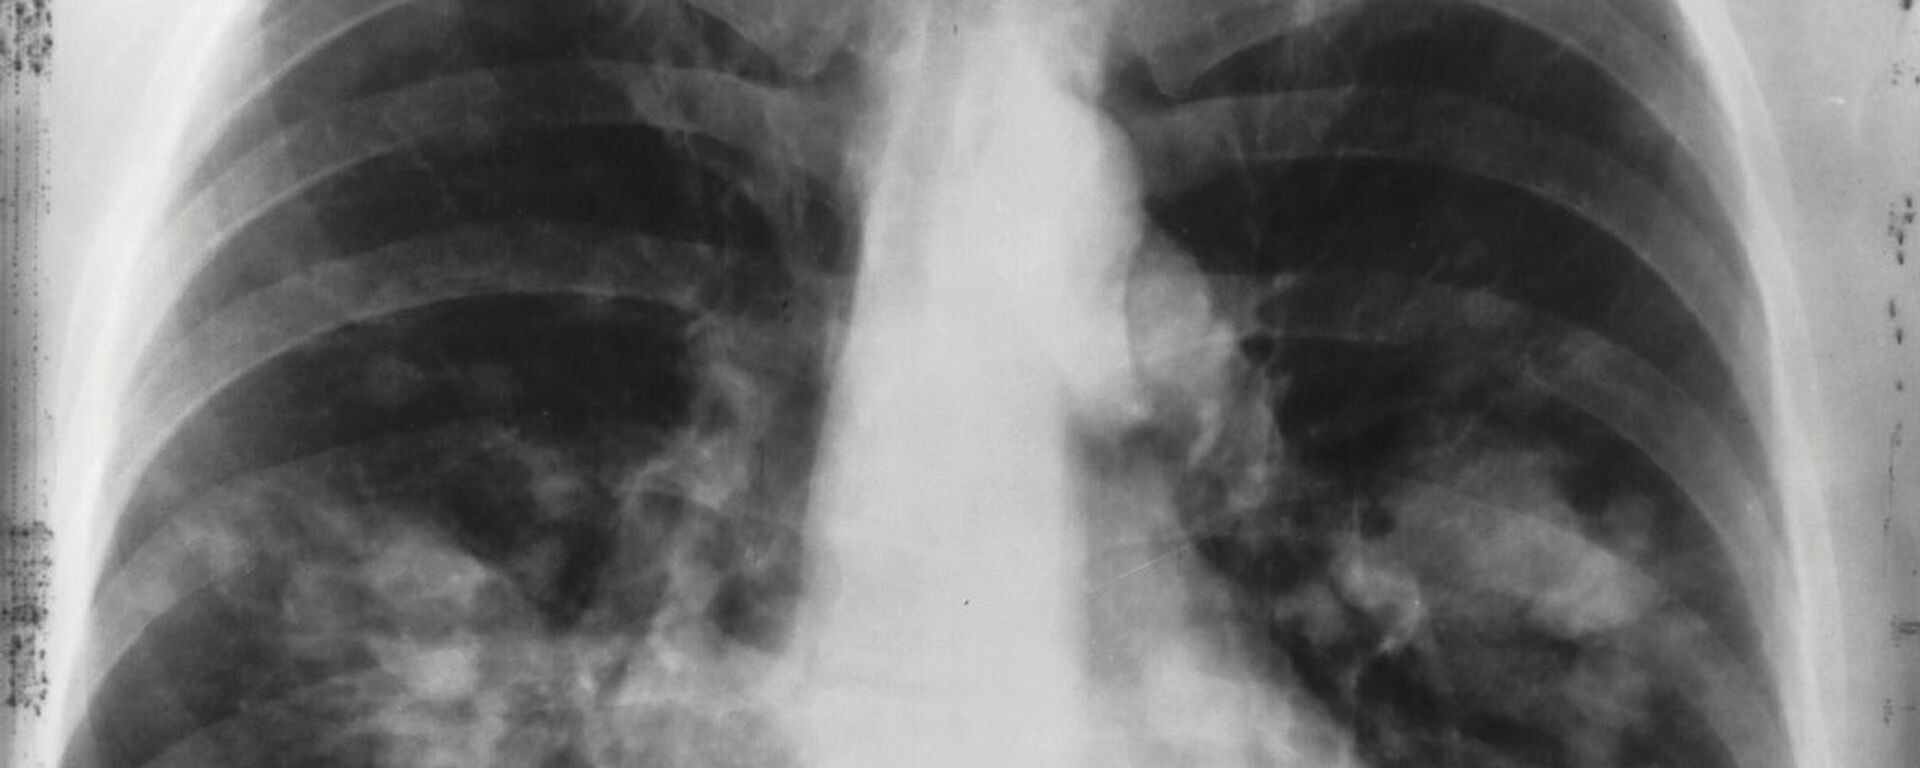

أشار الرئيس الروسي، فلاديمير بوتين، إلى نجاحات الطب الروسي في التعامل مع الأمراض السرطانية، داعيا إلى مكافحة أكثر فعالية للأمراض الأخرى. 18.02.2025, سبوتنيك عربي

وقال بوتين خلال اجتماع مع أعضاء الحكومة الروسية، تعليقا على تقرير نائبة رئيس الوزراء الروسي تاتيانا جوليكوفا: "عندما يتعلق الأمر بعلم الأورام، كما ترون، الاستجابة جيدة، ويستجيب نظام الرعاية الصحية لهذا الأمر بشكل جيد. ولكن بالطبع، نحن بحاجة إلى العمل بأقصى قدر ممكن من الاجتهاد على الأمراض الأخرى التي يتم تحديدها".وفي وقت سابق، أعلن علماء في المؤسسة الحكومية الروسية "روساتوم" عن تطويرهم لتقنية جديدة لإنتاج نظير طبي مشع يُسمى "تربيوم-161"، والذي يعد بفعالية أكبر في علاج السرطان مقارنة بالعلاجات الحالية.وتمكّن العلماء في معهد مواد المفاعلات في مدينة "زاريشني" في مقاطعة سيردلوفسك الروسية من إتقان تصنيع النظير المشع "تربيوم-161"، الذي سيسهم في إنتاج أدوية إشعاعية جيل جديد، تعِد بتقديم نتائج مبهرة في معالجة الأورام.علماء روس يطورون خلايا عصبية شبيهة بتلك التي تمتلك ذاكرة في دماغنا هل هناك علاقة بين شرب القهوة والشاي والإصابة بالسرطان؟